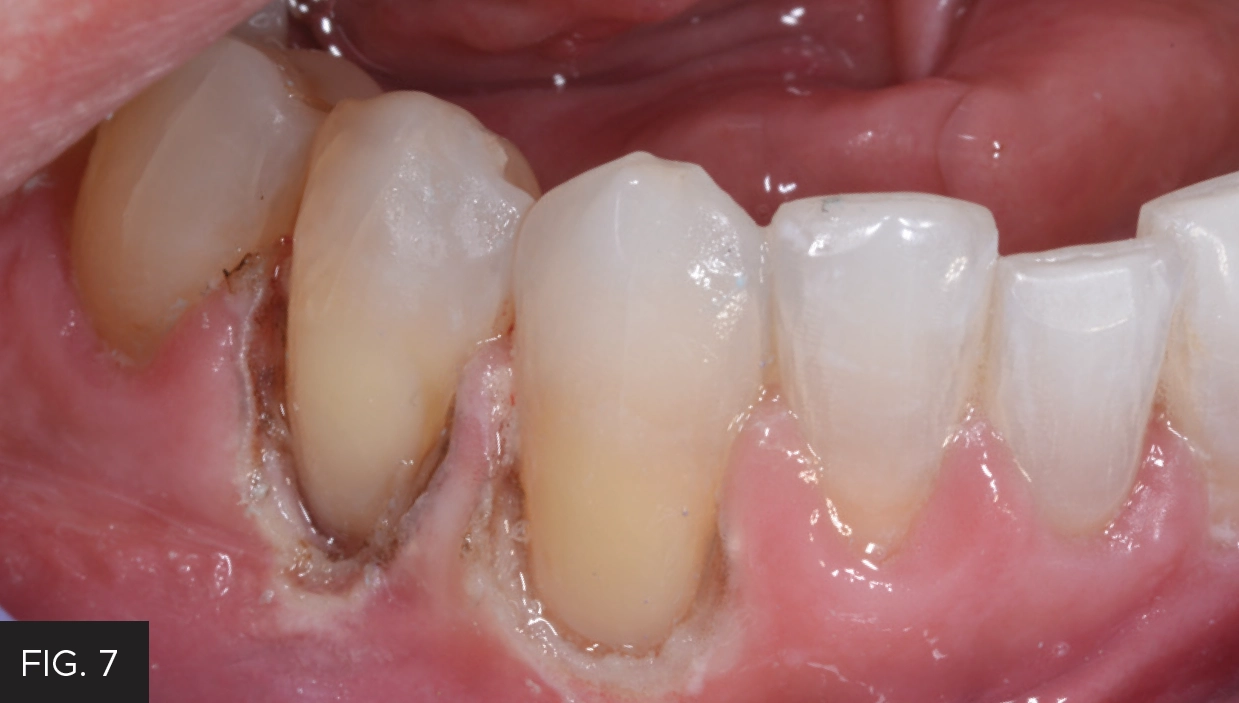

The preparation was then etched with 37% phosphoric acid, rinsed then lightly dried. G5™ All-Purpose Desensitizer (Clinician’s Choice) was scrubbed into the preparation to prevent post-op sensitivity, with the excess G5 blotted with a micro brush. A bonding agent was applied, thinned, and then light-cured with the Valo™ Grand (Ultradent™ Products, Inc.). Flowable composite was heated in the Calset™ Composite Warmer (AdDent) and placed along the cervical aspect of the preparation and light-cured, to establish a gap-free marginal seal. Additional flowable composite was then spread coronally to ensure thorough coverage of the cementum. This was followed by heated microfill composite, placed in increments and then using a REJ #04 (Clinician’s Choice) to completely fill the preparation. Care was taken before to smooth the composite as much as possible and remove excess before light-curing in order to minimize the amount of finishing time required. (FIG. 7)